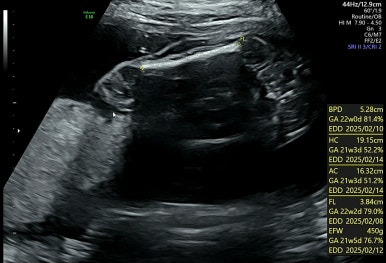

21주 1일

정밀초음파로 외형, 장기 등이 이상이 없는지 확인하는 시기이다.

머리부터 발끝까지 꼼꼼하게 검사를 하게 된다!

손발 등 너무 정교하게 생겨서 너무 신기하다!